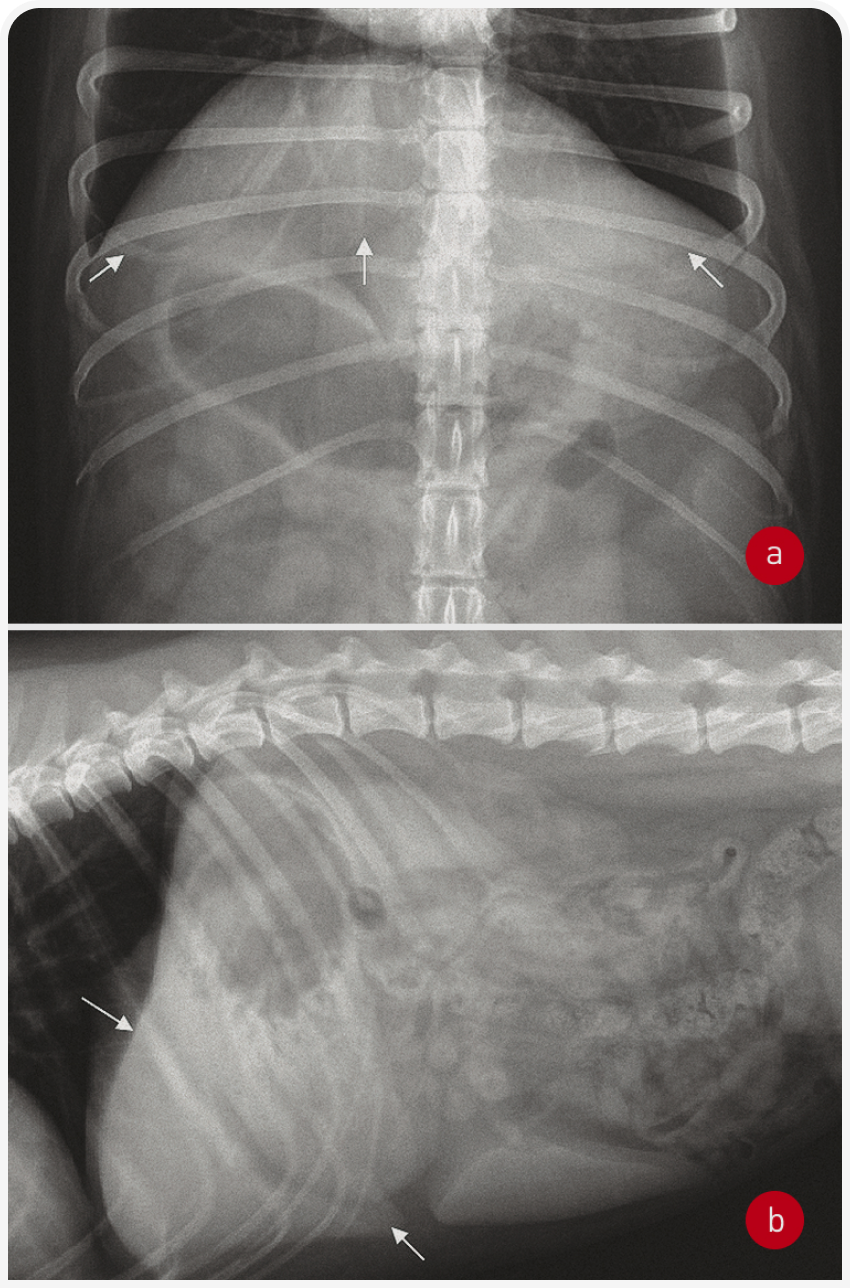

Рентгенография позволяет оценить размеры и контуры печени, но не изменения паренхимы (кроме скопления газов или минерализации). Для исследования нужно получить изображения брюшной полости на выдохе в двух ортогональных проекциях (боковой и вентродорсальной). Чтобы полностью визуализировать печень, важно включить в рентгенограмму брюшной полости краниальный край диафрагмы.

Силуэт печени невозможно отличить от диафрагмы, а каудально он ограничен желудком. Каудовентральный край нормальной печени острый (Рисунок 1). Оценивать размеры печени удобнее по желудочной оси; на боковой рентгенограмме печень должна быть видна между линией, проведенной под углом 90 градусов к позвоночнику, и линией, параллельной последней паре ребер. Если ось желудка смещена за пределы последней пары ребер или если каудальный край печени простирается до вентральной части желудка, это указывает на гепатомегалию. Если желудок смещен краниально, печень, по всей вероятности, маленькая, хотя такое явление в норме встречается у собак с глубокой грудной клеткой, таких как боксер, доберман, немецкий дог. При заболеваниях печени часто развивается асцит (скопление жидкости в брюшной полости), который в некоторых случаях может затруднять обследование печени. Однако асцит легко распознать на рентгенограммах брюшной полости по снижению четкости серозной оболочки, а в тяжелых случаях – по отвислому животу.

Объемные образования в печени могут деформировать контур печени и вызывать ряд изменений (вторичных патологических изменений вследствие сдавления или смещения окружающих тканей). Опухоль правых отделов печени смещает привратник каудомедиально, а центральных или левых отделов печени – искажает краниальный контур дна желудка.

В норме желчный пузырь на рентгеновском снимке не виден. Однако иногда у кошек вентральная часть желчного пузыря может распространяться за пределы вентрального края контура печени на серповидную жировую подушку (falciform fat); ее следует дифференцировать с объемными образованиями. Желчнокаменная болезнь часто вызывает минерализацию ткани печени, а при поражении внутрипеченочных желчных протоков на рентгенограмме появляются ветвистые тени (Рисунок 2).